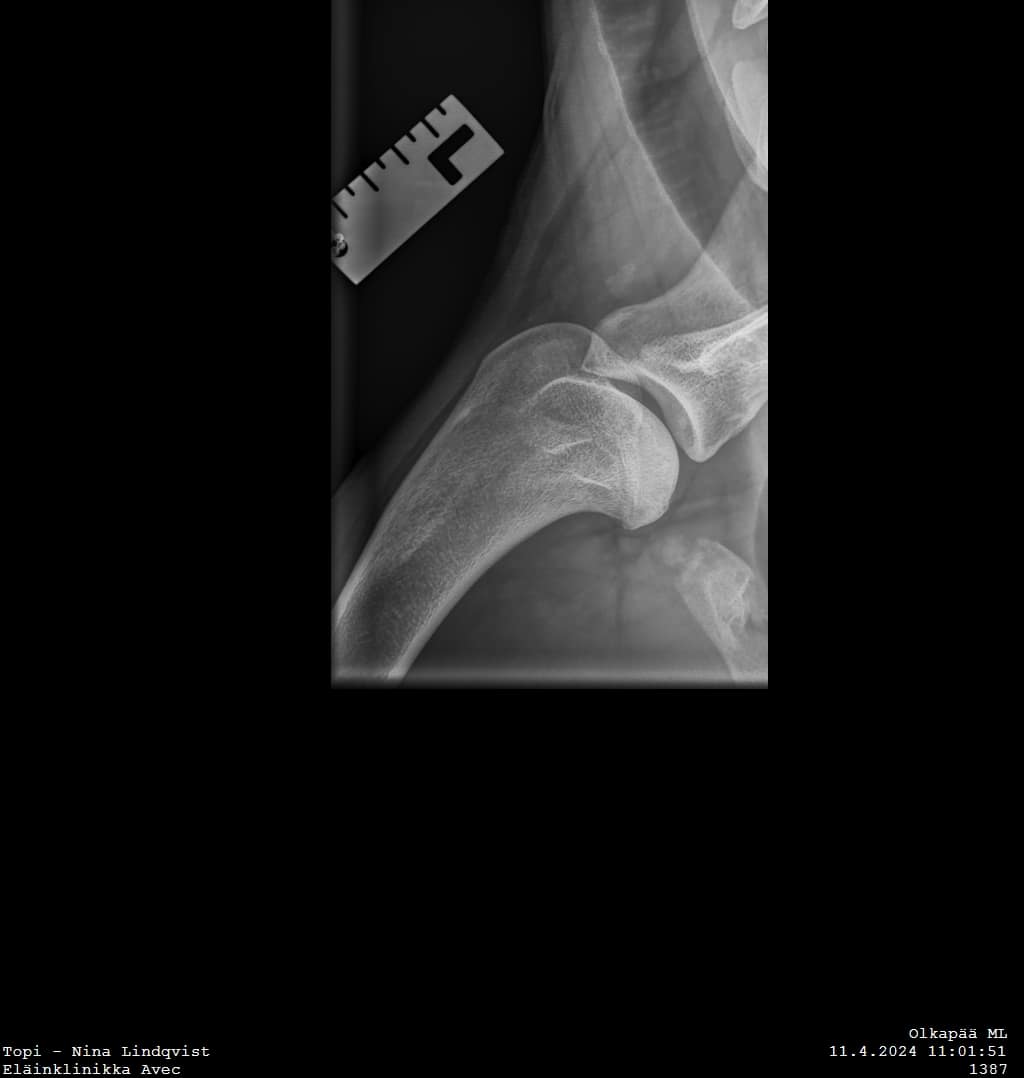

Topilta röntgenkuvattiin olat ja kyynärät. Kyynärissä ei ollut huomauttamista, ja molempien olkien tilanne on olkaluunpään osalta tosi hyvä. Parantuminen on edelleen käynnissä, eikä minkäänlaisia merkkejä nivelrikosta ole. Ja sitten se mutta. Vasemman olan glenoidaalikuopassa näkyy pieni röntgenharva alue. Olkanivelet myös ultrattiin, ei poikkeavia löydöksiä.

On mahdollista että Topilla on nyt sitten osteokondroosi myös tässä lapaluun alaosassa. Asian varmistamiseksi tarvittaisiin jälleen lisätutkimuksia tai jopa uusi tähystysleikkaus. Aiheuttaako tuo glenoidaalikuopas muutos nyt nämä kipuoireet vai ei, kas siinäpä kysymys. Varmaa diagnoosia emme siis tällä käynnillä saaneet.

Tässä on nyt hetki sulateltu uusimpia löydöksiä ja pohdittu jatkoa. Olen saanut näkemyksiä tilanteesta eri ortopedeiltä, ja kyllä ammattilaisten veikkaus on, että Topilla on osteokondroosi myös siellä lapaluun nivelkuopassa. Asian varmistaminen vaatisi jatkotutkimuksia ja niitä vielä pohditaan.